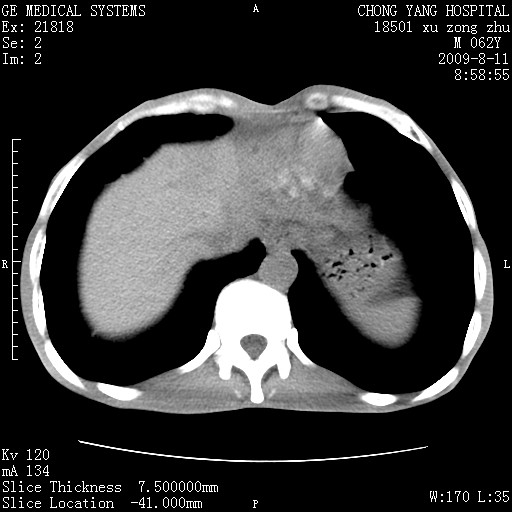

以下是引用杀毒软件在2009-8-11 16:35:00的发言:[br]肝内胆管扩张局限于左叶,胆管内有结石伴肝外胆管结石,胆管壁增厚呈弥漫性并发腹腔积液,胰腺边界模糊。[br][br]考虑---胆总管及肝内胆管结石继发胆管炎及胰腺炎,左肾下极囊肿,腹水。

以下是引用zjzjr在2009-8-11 17:35:00的发言:[br]肝内胆管扩张局限于左叶,胆管内有结石伴肝外胆管结石,胆管壁增厚呈弥漫性并发腹腔积液。[br][br]考虑---胆总管及肝内胆管结石继发胆管炎,左肾下极囊肿,腹水。